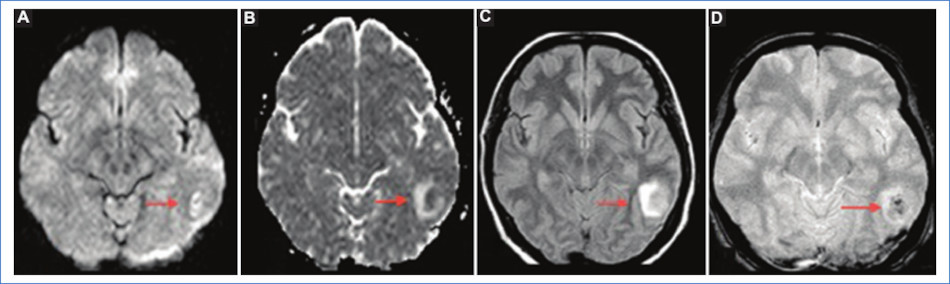

Hallazgos típicos: áreas con edema vasogénico caracterizadas por hiperintensidad en T2 y FLAIR e hipointensidad en T1 a nivel parieto-occipital bilateral. La difusión suele ser negativa, ya que se debe a edema vasogénico (Fig. 1). Sin embargo, cuando no se realiza un diagnóstico precoz puede evolucionar a edema citotóxico (irreversible), en cuyo caso dichas áreas presentan restricción en difusión con caída de señal en el mapa de ADC, o puede asociarse a la existencia de hemorragia subaracnoidea (HSA)1,4.

Hallazgos atípicos: es casi tan habitual como la clásica. Hay afectación de los lóbulos frontales, el tronco, el cerebelo y los ganglios basales. La mayoría de los casos remiten por completo. Las lesiones irreversibles (edema citotóxico) ocurren en el 15% de los casos y se caracterizan por restricción en difusión (Fig. 2)4.